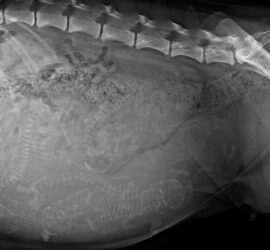

G-chen auf der Zielgeraden